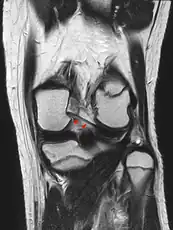

- Posterior meniscofemoral ligament on MRI, coronal

- Posterior meniscofemoral ligament (Wrisberg) behind the posterior horn of the lateral meniscus close to its insertion. Sometimes wrongly interpreted as a meniscal tear.